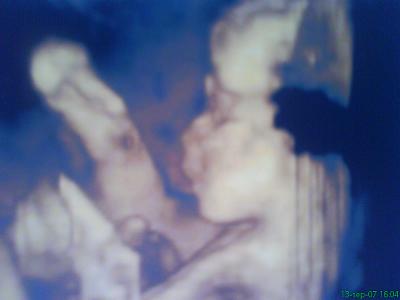

A második képen nyitva van a szeme is